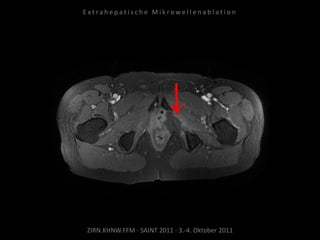

Verlaufskontrolle:

MRT 12.10.2010

Restvitalität dorsal der Harnblase.

Erneute Ablation am 04.11.2010:

2 Nadelpositionen.